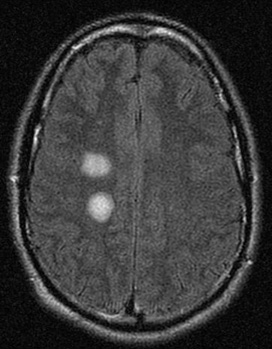

RNM cranioencefálica: fitas corticais (hiperintensidade nos giros corticais) em um paciente com doença de Creutzfeldt-Jakob em imagens ponderadas por difusão

Do acervo pessoal de Leo H. Wang; usado com permissão